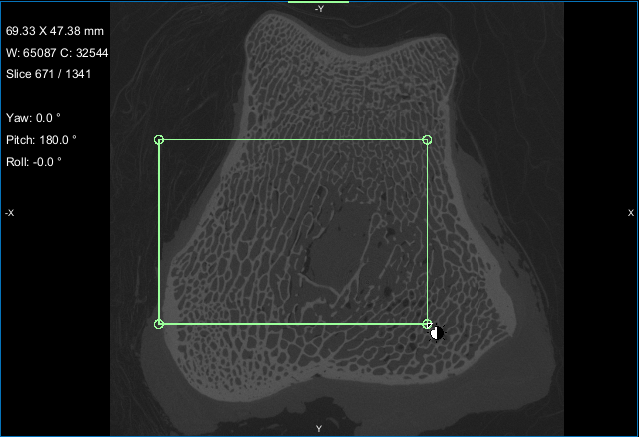

- Create a box that either entirely or partially encloses the region of interest as follows:

- Click the Box button in the Shapes panel.

A new Box shape appears in the Data Properties and Settings panel. Click the Eye icon to show the box in the workspace views.

- Adjust the box in the 2D and/or 3D views of the region of interest, as required.

You can resize and rotate the box, as well as change its position with the available control points (see Editing Shapes).

- Choose the box that encloses the area that you want to include in your analysis in the Area box drop-down menu.